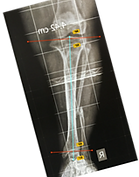

Acute osteomyelitis

Acute osteomyelitis can be a devastating or even fatal disease with a high rate of sequelae, especially in resource-poor countries. AHOM is typically a monomicrobial disease, Staphylococcus aureus (S. aureus) remains the most common pathogen globally notwithstanding that Methicillin-resistant Staphylococcus aureus (MRSA) has an increased.

Early diagnosis is the key to successful management and the prevention of long-term sequelae.

the management for AHOM includes Empiric IV (intravenous) antibiotics based on the most likely causative agents, Source control: specimens for microscopy, culture and sensitivity (MCS).

If there is no response to medication within days, an intervention such as draining an abscess might speed up the healing process, A corticotomy can be performed for intraosseous collections, and drains are routinely placed. Bone drilling is required in patients with subperiosteal or intramedullary abscesses

The limb segment should be protected in the first six weeks to prevent a pathological fracture.